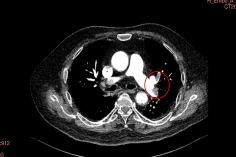

左肺动脉上、下叶动脉血栓(术前影像)

肺动脉主干血栓形成(术前影像)